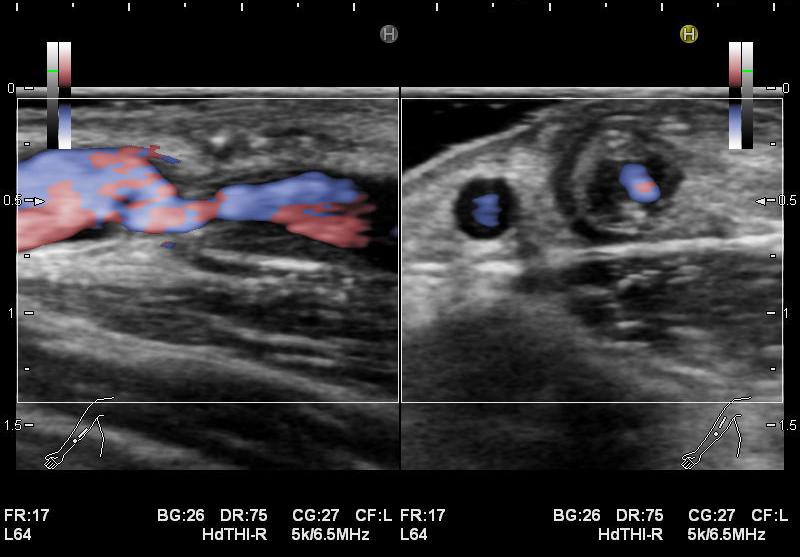

・静脈系の観察

吻合部から中枢へ向かって走査し、血管の走行や太さ、血管までの深さ、狭窄や石灰化、血栓等の有無を観察しています。長軸断面、短軸断面それぞれで観察し、また、カラードプラも使用しできるだけ正確に、血管内の状況を把握するようにしています。